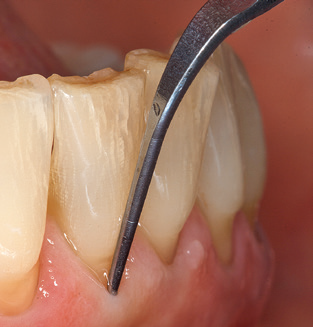

Das aktuelle Arbeitskonzept für die UPT

Die Aktualisierung der Anamnese stellt im Rahmen der UPT eine zentrale Maßnahme dar, sie sollte mindestens einmal jährlich erfolgen. Sie dient dazu, mögliche neue Risikofaktoren zu erkennen und zu dokumentieren. Vor allem dann, wenn ein Patient langjährig betreut wird, ist es wichtig, zu erfahren, ob sich patientenspezifische und allgemeinmedizinische Risikofaktoren verändert haben. Hier sollte an erster Stelle an ein erhöhtes Risiko durch Diabetes gedacht werden, aber auch andere allgemeinmedizinische Erkrankungen (kardiovaskuläre Erkrankungen und Neoplasien) können aufgrund der erfolgten Therapien und der notwendigen Medikamenteneinnahme zu einem veränderten Risikoprofil führen. Das Update der Anamnese ist also auch im Rahmen der UPT sehr wichtig, um gegebenenfalls aufgrund eines veränderten Risikoprofils eine Veränderung des Behandlungsintervalls zu veranlassen. Im nächsten Schritt ist es wichtig, der Diagnostik besondere Aufmerksamkeit zu schenken. Die Instrumentation ist zwar ein zentraler Bestandteil der UPT, in keinem Fall sollte sie aber Bestandsaufnahme und Dokumentation verdrängen. Für die Diagnose ist dabei der parodontale Befund unerlässlich, eine Zunahme der Sondierungstiefen und eine Erhöhung des BOP­Index sind zentrale Indikatoren für eine Progression parodontaler und periimplantärer Erkrankungen. Zum Erheben der benötigten Daten darf daher nicht davor zurückgeschreckt werden, auch Implantate zu sondieren. Dabei ist es wichtig, dass hierfür millimeterskalierte PAR­Sonden verwendet werden. Für die Sondierungsbefunde an natürlichen Zähnen haben sich seit Jahrzehnten metallische Sonden bewährt. Bei Implantaten ist die Herausforderung für das Erheben korrekter und reproduzierbarer Sondierungsbefunde größer. Da es durch die Diskrepanz von Implantatdurchmesser und Kontur der Suprakonstruktion regelmäßig zu einer Überkonturierung der Suprastruktur kommt, sind für Sondierungen an Implantaten flexible, aber dennoch millimeterskalierte Son­ den sehr sinnvoll (z. B. Colorvue Kit PCV11KIT6, Hu­Friedy; Abb. 4).

Abb. 4: Für das Sondieren an dentalen Implantaten sind biegsame, millimeterskalierte Sonden empfehlenswert (z.B. Colorvue Kit PCV11KIT6, Hu-Friedy). – Abb. 5a und b: Eine gerade Arbeitsspitze (1P, W&H Dentalwerk Bürmoos GmbH) ist universell für die Instrumentierung natürlicher Zähne geeignet. – Abb. 6: Für die Bearbeitung schwer zugänglicher Bereiche der Zahn- und Wurzeloberflächen (z.B. Furkationen) bieten sich gebogene Arbeitsspitzen (3Pr/3Pl, W&H Dentalwerk Bürmoos GmbH) an. – Abb. 7: Die spitz zulaufende sechseckige Implantatreinigungsspitze (1I, W&H Dentalwerk Bürmoos GmbH) ermöglicht eine atraumatische und effiziente Reinigung der Kronen- und Abutmentoberflächen. – Abb. 8: Für die manuelle Instrumentierung der Implantatoberflächen sind Titan- oder Carbonküretten geeignet.

Die gute Ausleuchtung des Arbeitsfeldes stellt eine wesentliche Erleichterung dar. Bei dem von den Autoren genutzten System ist dies gelungen, indem ein 5­facher LED­Ring in das Handstück integriert wurde. Natürlich werden für dieses System unterschiedliche Arbeitsspitzen für die jeweiligen Indikationsbereiche angeboten. Eine gerade, universell einsetzbare Spitze ist das Basisinstrument zur maschinellen Instrumentierung natürlicher Zähne (Abb. 5a und b). Für schwer zugängliche Bereiche im Seitenzahnbereich werden gebogene Spitzen angeboten, die auch einen Zugang zu freiliegenden Furkationen ermöglichen (Abb. 6).